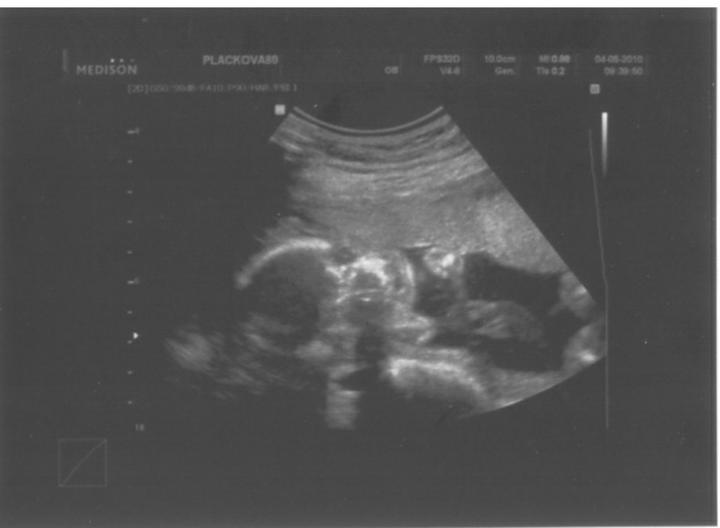

Velký UTZ ve 20 týdnu za námi_vše v pořádku....

asi budeme mít holčičku 🙂